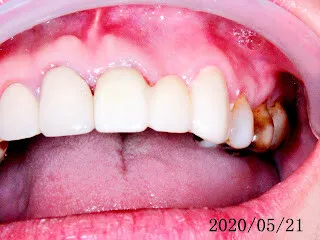

假牙材質2臨床案例...不同的假牙材質+牙齦萎縮